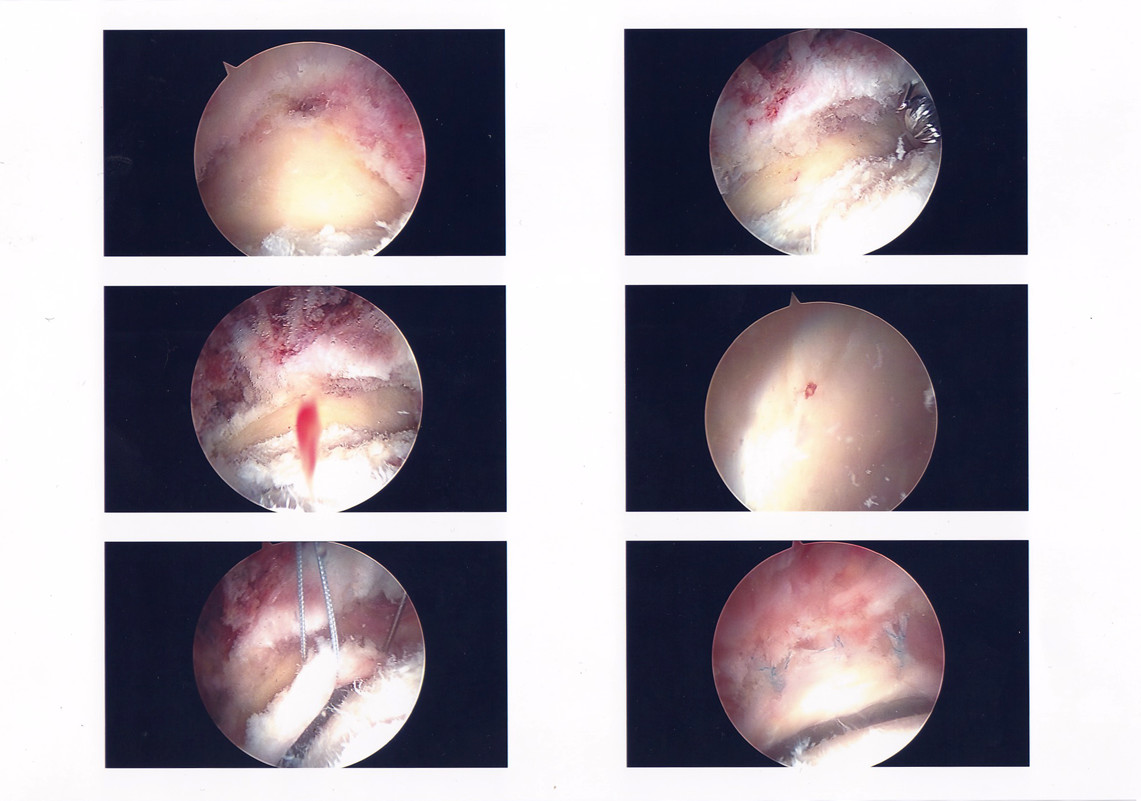

Below is a gallery of the scopes from my surgery. Starting with the initial scope to the Dr. repairing my labrum (if you look at the slide show, it’s the blue thread), then going in and removing the tissue built up in my hip joint and sculpted my hip socket.